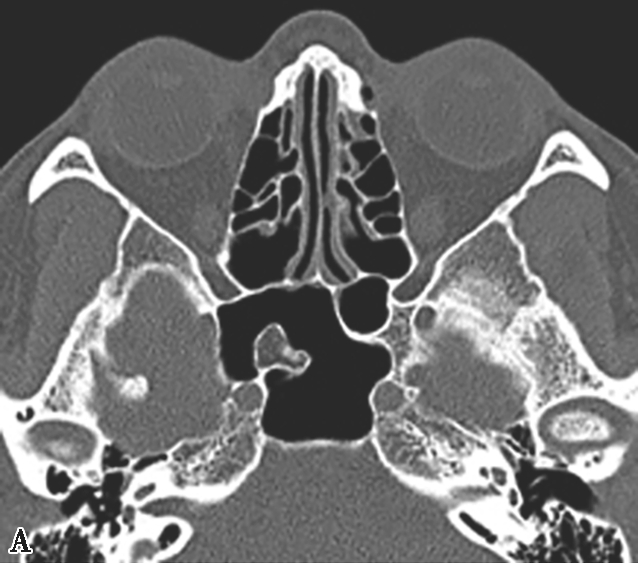

鼻丘气房位于筛漏斗的前上部,与泪骨、上颌骨、筛骨、额骨、鼻骨关系密切。是由筛漏斗直接发展而来。鼻丘气房通常位于额窦底的前部,构成额隐窝的前壁,大小不一,过大、过多可妨碍额窦引流,引起额窦炎。鼻丘气房和钩突眶内壁附着点之间的关系非常密切。当钩突与眶内壁没有附着点时,鼻丘气房不存在;当钩突与眶内壁仅有一个附着点时,鼻丘气房存在;当钩突与眶内壁有两个及以上附着点时,形成上下两个气房,在冠状面观察,偏下的气房称为鼻丘气房,偏上的气房称为额气房,两者内壁均由钩突构成(图1-3-1)。

图1-3-1 鼻丘气房及额气房CT解剖

A~C.鼻丘气房(五角星),额气房(星),钩突(白箭),筛骨纸板(箭头)